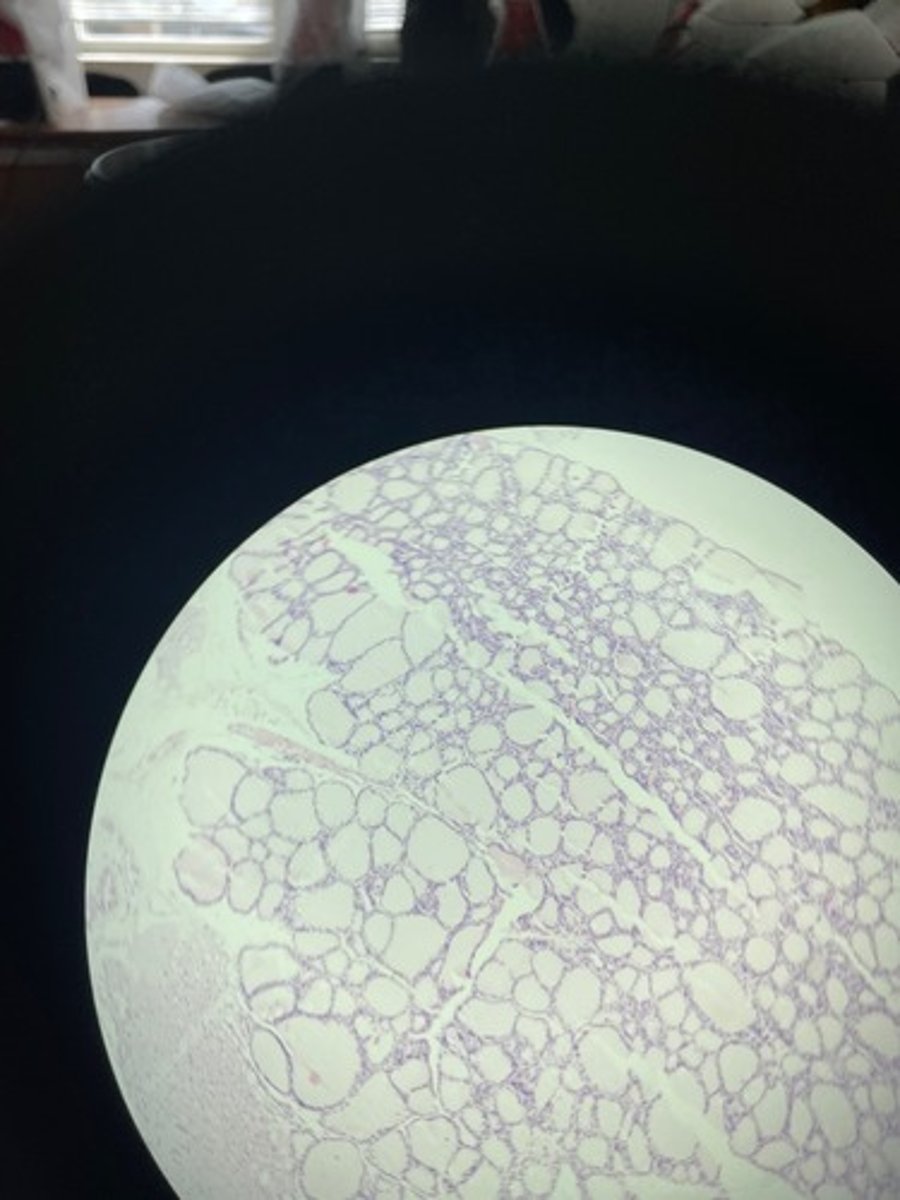

Thyroid gland HE

Thyroid gland HE

Thyroid gland HE

Thyroid HE

Thyroid HE